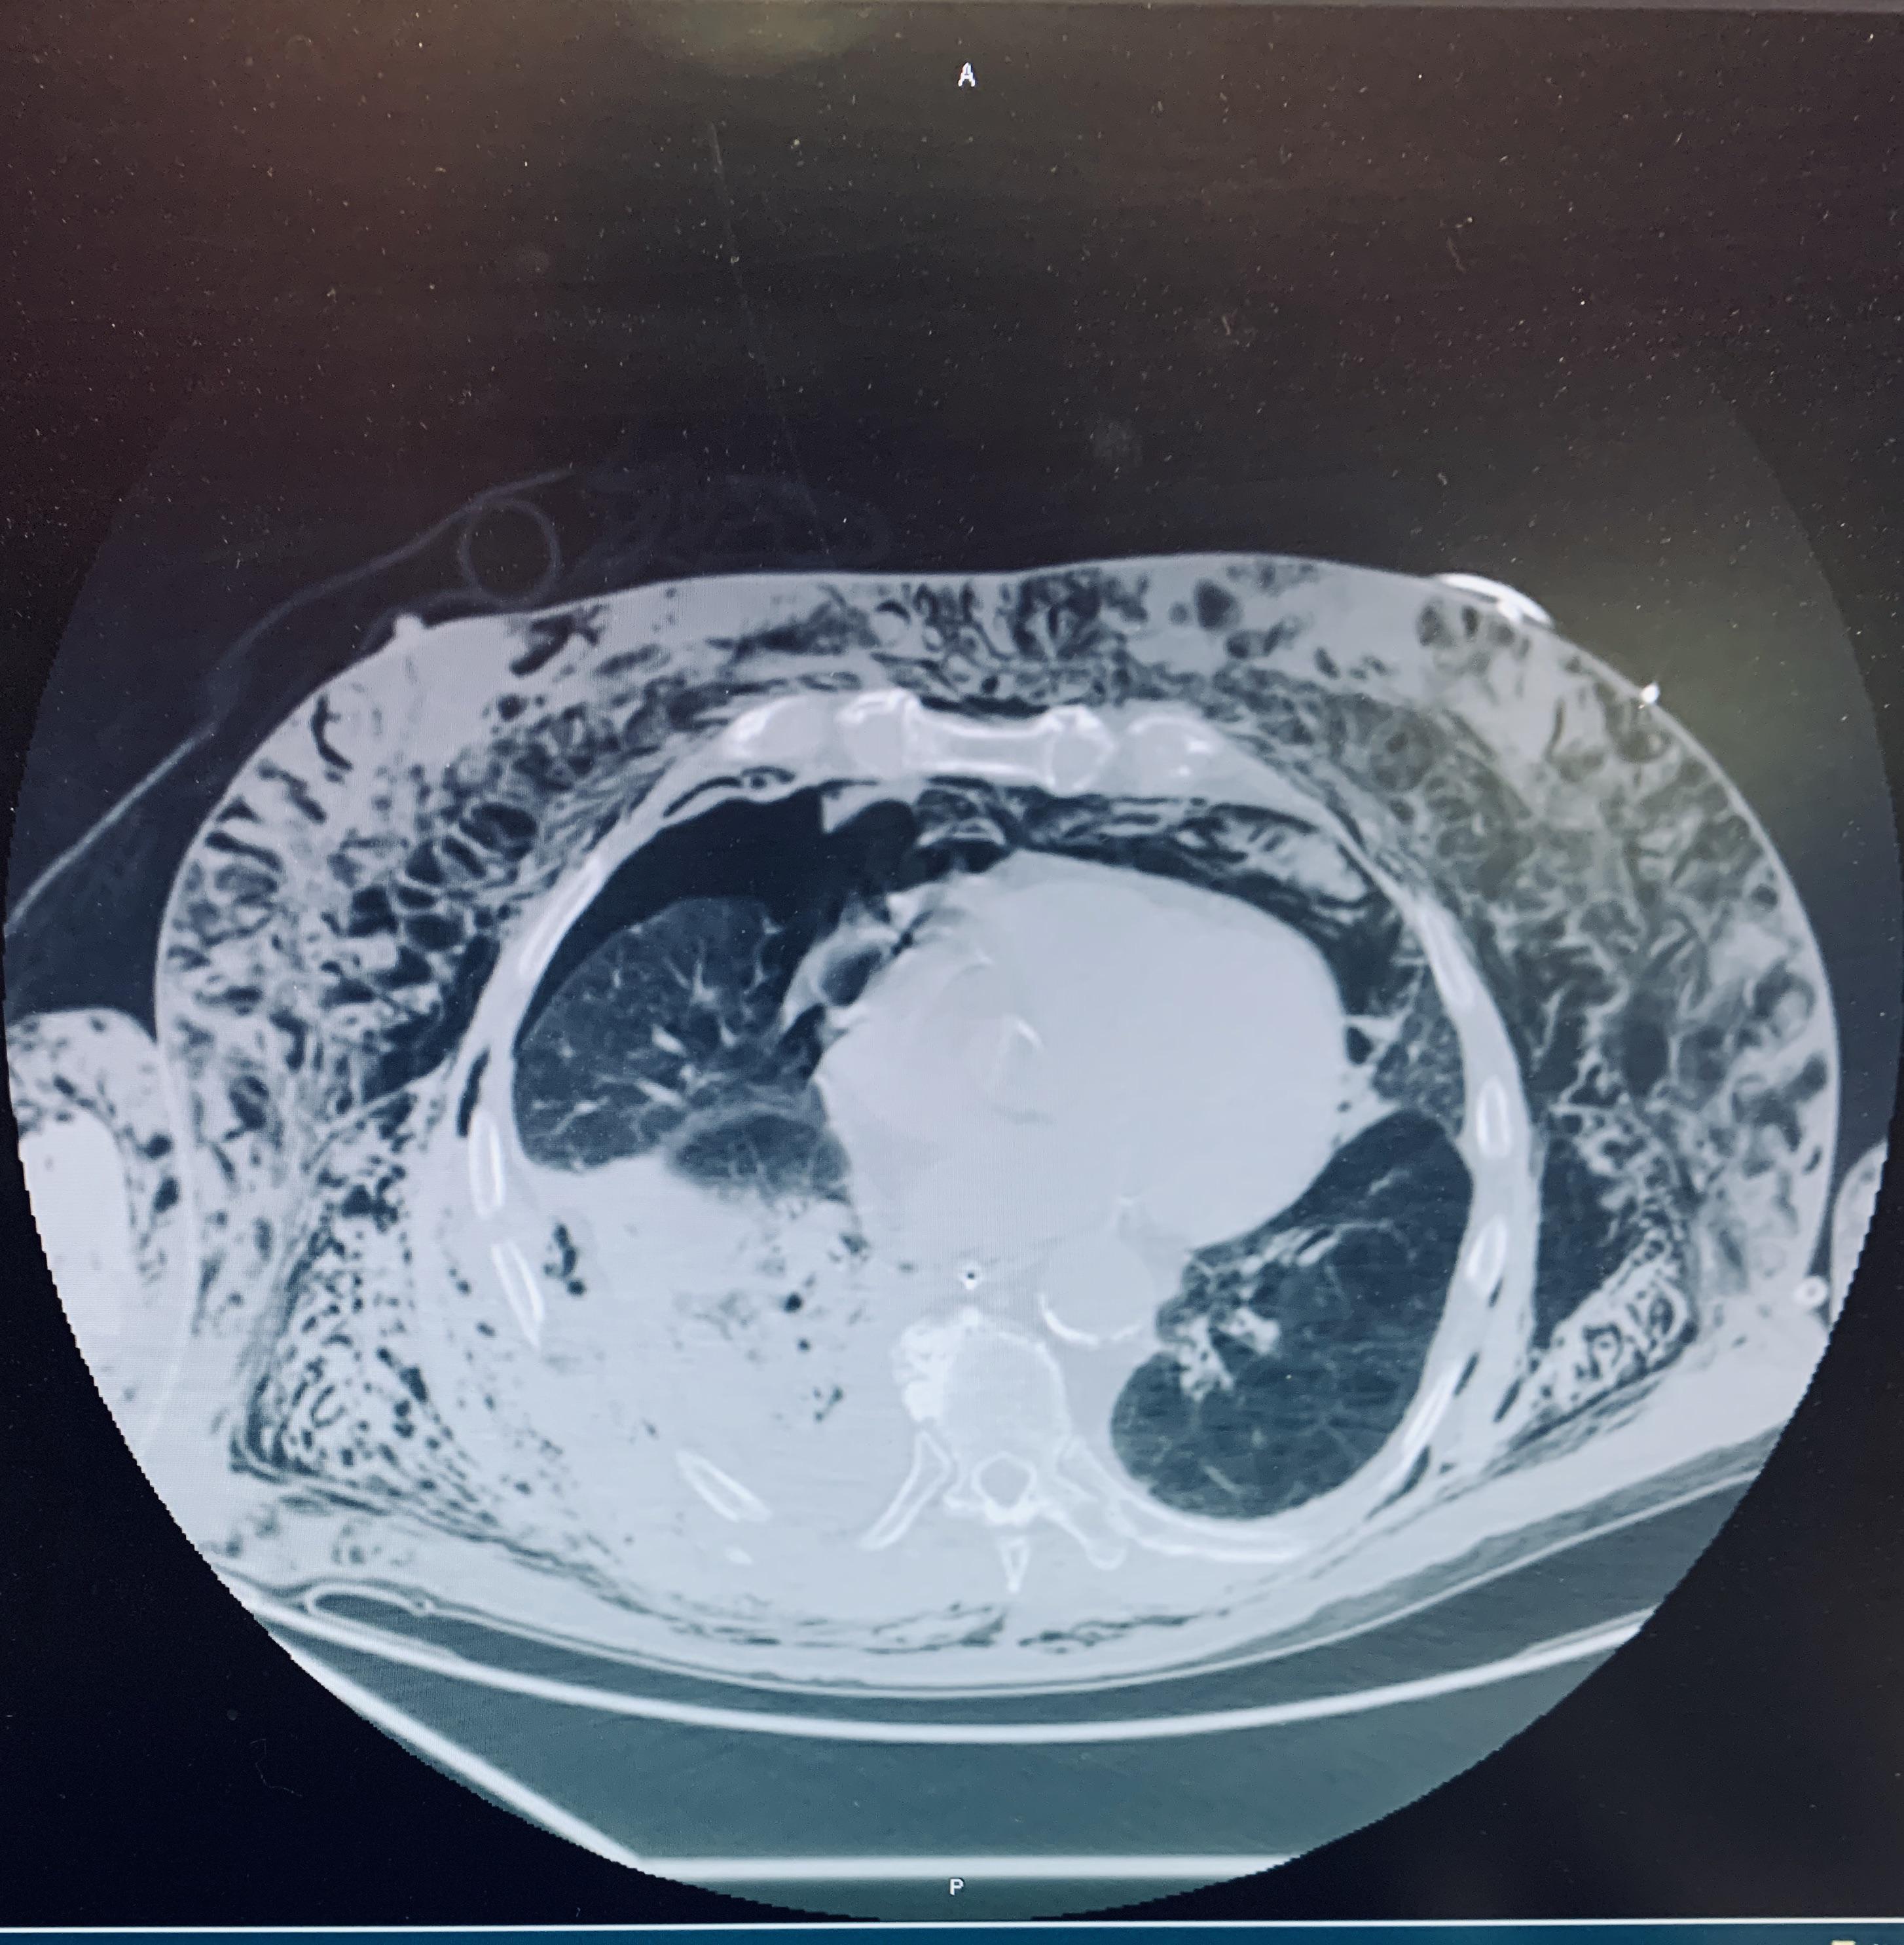

Rib Fracture With Subcutaneous Emphysema . learn about the causes, symptoms, diagnosis, and treatment of rib fractures, which are common injuries. ct of the chest shows pneumomediastinum (blue arrow), left apical pneumothorax (pink arrow), and subcutaneous emphysema (red. subcutaneous emphysema is a condition in which air becomes trapped under the subcutaneous layer of the skin. [9] in fact, 27% of patients who have rib fractures also have. subcutaneous emphysema is often observed by clinicians in the context of pneumothorax. the most common cause of se was pneumothorax with background of copd and surgery in grade 5, trauma due to rib. The main symptoms are edema and. the condition may also occur when a fractured rib punctures a lung;

Rib Fracture With Subcutaneous Emphysema the most common cause of se was pneumothorax with background of copd and surgery in grade 5, trauma due to rib. ct of the chest shows pneumomediastinum (blue arrow), left apical pneumothorax (pink arrow), and subcutaneous emphysema (red. subcutaneous emphysema is often observed by clinicians in the context of pneumothorax. subcutaneous emphysema is a condition in which air becomes trapped under the subcutaneous layer of the skin. the most common cause of se was pneumothorax with background of copd and surgery in grade 5, trauma due to rib. The main symptoms are edema and. learn about the causes, symptoms, diagnosis, and treatment of rib fractures, which are common injuries. the condition may also occur when a fractured rib punctures a lung; [9] in fact, 27% of patients who have rib fractures also have.

Trauma Chest X Ray With Rib Fractures And Subcutaneous Emphysema My Rib Fracture With Subcutaneous Emphysema [9] in fact, 27% of patients who have rib fractures also have. subcutaneous emphysema is a condition in which air becomes trapped under the subcutaneous layer of the skin. ct of the chest shows pneumomediastinum (blue arrow), left apical pneumothorax (pink arrow), and subcutaneous emphysema (red. the condition may also occur when a fractured rib punctures a. Rib Fracture With Subcutaneous Emphysema.